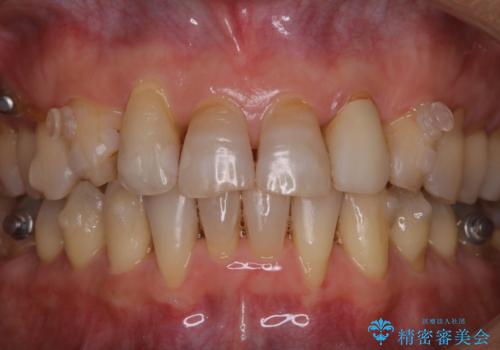

- マウスピース矯正中(インビザライン)に着色落としをしたいとのことでした。PMTC60分コースを行いました。

PMTC(保険外治療)は、毎日の歯磨きで落としきれない汚れや、コーヒ、紅茶・タバコのヤニなどの着色も除去します。目には見えない歯と歯の間・歯肉の境目・インビザライン中はアタッチメント周囲などに残っているプラーク(歯垢)もしっかり取り除きます。PMTCでは専門的な機械や材料を使用して、徹底的に汚れを除去するため、虫歯・歯周病・口臭予防などにつながります。

またPMTCを行うことで、ご自身本来の歯の色になり自然な明るさになります。

口元が自然な明るさになることで、より清潔感のある印象になるため結婚式・行事やイベント前などにもPMTCを行うはおすすめです。